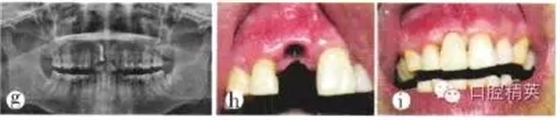

(3)種植修復(fù):拔牙后3個(gè)月行種植修復(fù)。全景片顯示牙槽骨高度及種植空間基本正常(圖1e)。植入1顆3.3 mm×10 mm瑞士ITI種植體;由于唇側(cè)根尖區(qū)骨質(zhì)破壞,致根部種植體暴露約2 mm,取舌側(cè)骨板碎塊充填,嚴(yán)密縫合。術(shù)后x線(xiàn)全景片顯示植體位置、高度等均較理想(圖1f)。種植術(shù)后3個(gè)月行上部修復(fù),全景片顯示植體周?chē)琴|(zhì)致密,骨高度尚可(圖1g)。種植體愈合良好、穩(wěn)固,袖口成形較好(圖1h)。完成種植義齒上部修復(fù)(圖1i)。隨訪(fǎng):種植修復(fù)完成后患者對(duì)咀嚼效率和美觀效果均較滿(mǎn)意?,F(xiàn)已完成種植修復(fù)3年余,修復(fù)體穩(wěn)固,咀嚼效率高,牙齦形態(tài)良好,美觀效果較好。

圖1e種植術(shù)前全景片;f種植術(shù)后全景片;g種植上部修復(fù)前全景片;h牙齦袖口形態(tài);i種植修復(fù)完成